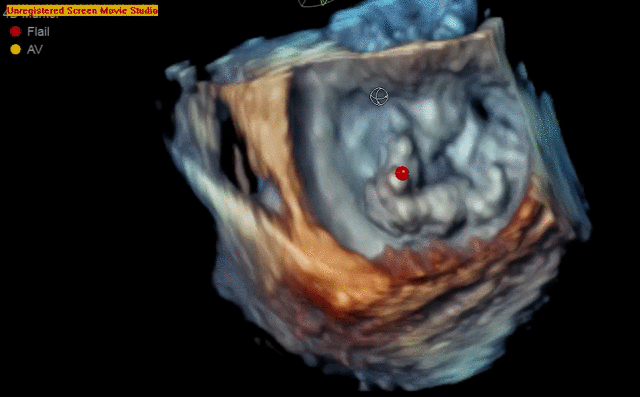

4D color imaging with the 4Vc-D probe

4D TEE color imaging with Vmax